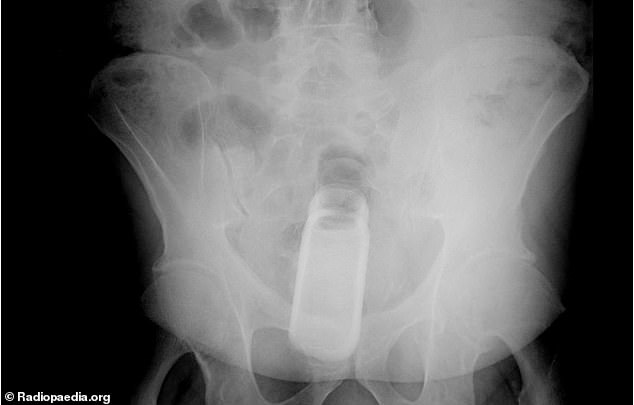

Every year, Americans end up with different types of objects stuck in their rectums.

According to the US Consumer Product Safety Commission’s database of emergency room visits for 2017, there are a lot of bizarre items that people have inserted into their holes.

It was found that the rectum is the most common place for bizarre items to get stuck. Some of the objects include household items such as aerosol can, plastic pill bottle, beer bottle, and a plastic cigar holder.